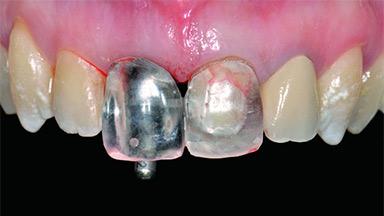

Replacement of a Failing Upper Right Central Incisor, Ridge Preservation and Late Placement of a NC Bone Level Implant

A 30-year-old patient presented at our clinic with a chief complaint of pain in her endodontically treated right maxillary central incisor (tooth 11) with a post-and-core and a fixed single crown. She had a very high lip line, a medium to thin soft-tissue phenotype, and a medium scalloped gingival contour. She also had high esthetic expectations because of her young age and beautiful smile. However, her expectations were realistic and she understood the risks of the treatment. At the initial clinical examination there was a slight mobility of tooth 11; no fistula was observed. The patient also had a single crown on the adjacent tooth 21. Both restorations were old and esthetically deficient. A digital periapical radiograph showed a very small periapical radiolucency, a thick intraradicular post, and no separation between root fragments.